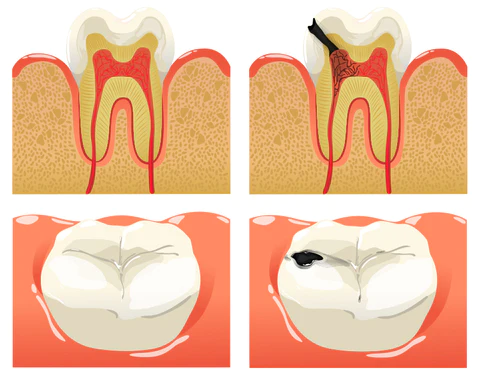

Dental caries develop when germs damage tooth enamel and gradually penetrate into the dentin and even the pulp. This can result in bad breath, toothaches, weakened teeth, and potential tooth loss. The presence of caries often triggers a chain reaction, causing healthy teeth to be affected as germs spread to adjacent teeth.